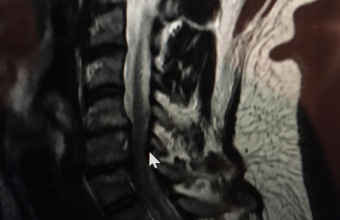

МРТ-знімок шийного відділу хребта Марата Кухара

- У палаті лежав, рукою поворухнути не міг. Я посивів навіть тоді. За попередніми показниками, ніби, виключили інсульт. Але з’ясувати, що відбувається зі мною без серйозної діагностики не могли. Зранку скерували на МРТ голови, аби кінцево переконатися, що інсульту немає. Я попросив зробити також МРТ шиї, оскільки вже сюди потрапив. Інсульт виключили, а з МРТ шиї зробили висновок, що в мене сильне зміщення хребців С5-С6, С6-С7. Діагноз - міжхребцевий остеохондроз шийного відділу хребта, грижі МХД С5-С6, С6-С7, спондельоз С 6, вторинний цервікальний стеноз.

- Ні. Він - фахівець з великим досвідом. А кожна людина - індивідуальна, і ситуація в мене була дуже непроста. Знімок МРТ збільшуєш, а там не видно проміжку між хребцем і спинним мозком. Я ще тоді ходив у фіксуючій пов’язці на шиї. Імунітет був знищений медикаментами. Тобто лікар взяв мене в дуже поганому стані.